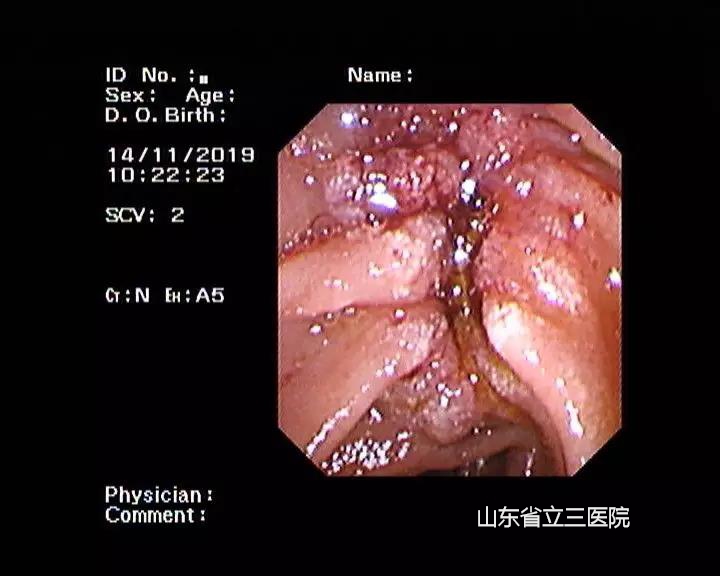

患者手術(shù)前經(jīng)過(guò)內(nèi)鏡檢查確診十二指腸乳頭及壺腹部腺癌

省立三院肝膽外科結(jié)合患者體征特點(diǎn),與患者家屬充分溝通后,在11月14日、15日先后為患者進(jìn)行了兩次內(nèi)鏡下光動(dòng)力手術(shù)治療。手術(shù)過(guò)程中,張锎主任與團(tuán)隊(duì)密切配合,運(yùn)用嫻熟的ERCP技術(shù)將半導(dǎo)體激光插入患者膽總管下段及十二指腸乳頭處,對(duì)腫瘤進(jìn)行照射,并在膽總管內(nèi)放置了塑料支架,保證患者膽汁流出通暢。兩次手術(shù)過(guò)程均迅捷順利,患者術(shù)后快速恢復(fù),2020年1月8日來(lái)院復(fù)查時(shí),發(fā)現(xiàn)十二指腸乳頭腫瘤已經(jīng)壞死脫落,手術(shù)完全達(dá)到了預(yù)期效果。